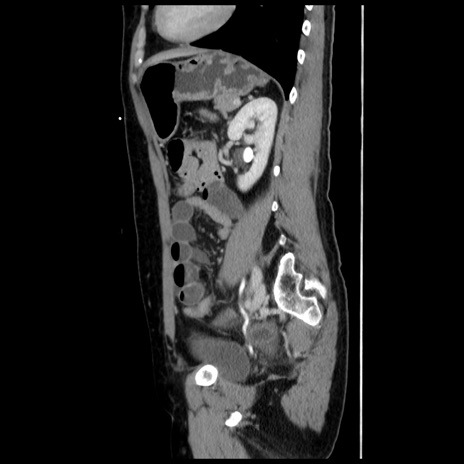

横断像

冠状断像